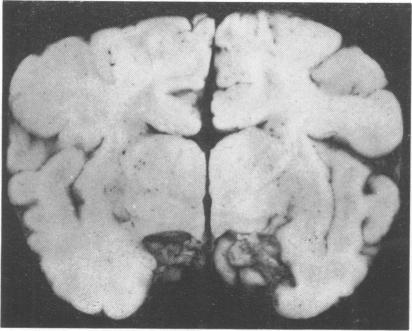

Two unique cases of the syndrome of absent abdominal muscles with central nervous system involvement are presented. Microcephaly, polymicrogyria, and cerebellar heterotopiae were present in both. In case 1 there was also absence of the corpus callosum and agenesis of the cerebellar vermis. In case 2 a count of anterior horn cells in the spinal cord showed a reduction of approximately 50% in the lower thoracic region. The pertinent literature is briefly discussed. The findings in the nervous system suggest that the syndrome is the result of defective embryogenesis during the first trimester.

本文报告了两例伴有中枢神经系统受累的腹直肌缺如综合征的独特病例。两例均存在小头畸形、多小脑回和小脑异位。病例1还存在胼胝体缺如和小脑蚓部发育不全。病例2脊髓前角细胞计数显示下胸段减少约50%。对相关文献进行了简要讨论。神经系统的发现表明,该综合征是孕早期胚胎发育缺陷的结果。